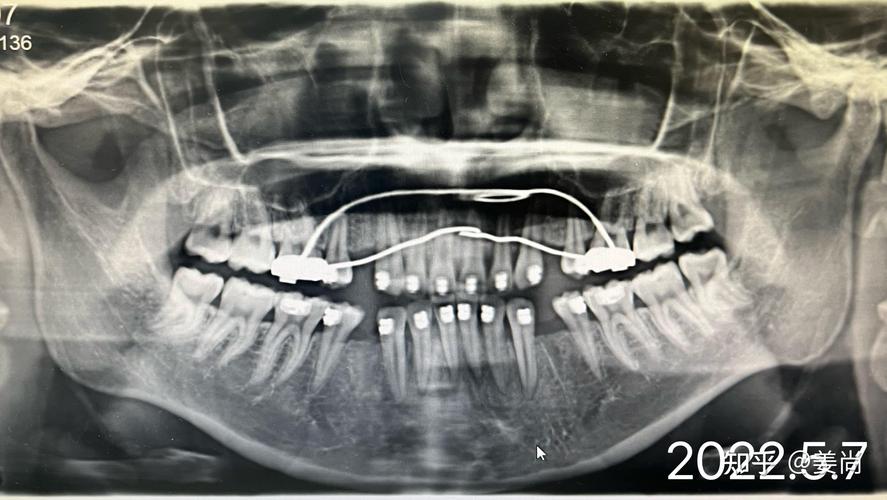

口腔正畸X光检查主要分为三类,各有其独特价值,曲面断层片(全景片)是最常用的基础检查,能一次性显示全口牙齿、牙槽骨、上下颌骨及部分颌面部结构,可观察是否有埋伏牙、多生牙、牙根吸收、牙槽骨骨密度异常等问题,辐射剂量低(约0.02mSv),相当于自然环境中2-3天的辐射量,适合常规筛查,头颅侧位片则是正畸诊断的“测量核心”,通过标记特定的解剖点(如蝶鞍、鼻根、上齿槽座点等),可定量分析上下颌骨的长度、宽度、高度比例,判断是否存在上颌前突、下颌后缩、面部不对称等问题,同时测量牙齿的倾斜角度、覆盖覆合程度,为矫治目标提供数据支持,CBCT(锥形束CT)则凭借三维成像优势,成为复杂病例的“精准导航”,能清晰显示牙根在颌骨内的位置、方向、形态,以及埋伏牙的萌出路径、骨量分布,适用于正颌手术前评估、种植体植入规划、疑难阻生牙拔除等场景,辐射剂量稍高(约0.1-0.3mSv),但单次检查仍在安全范围内,医生会严格掌握适应症。

| 曲面断层片 | 观察全口牙齿、牙槽骨、颌骨大体形态;筛查埋伏牙、多生牙、牙根吸收 | 辐射低、快速、全景显示 | 二维成像,细节分辨率低 |